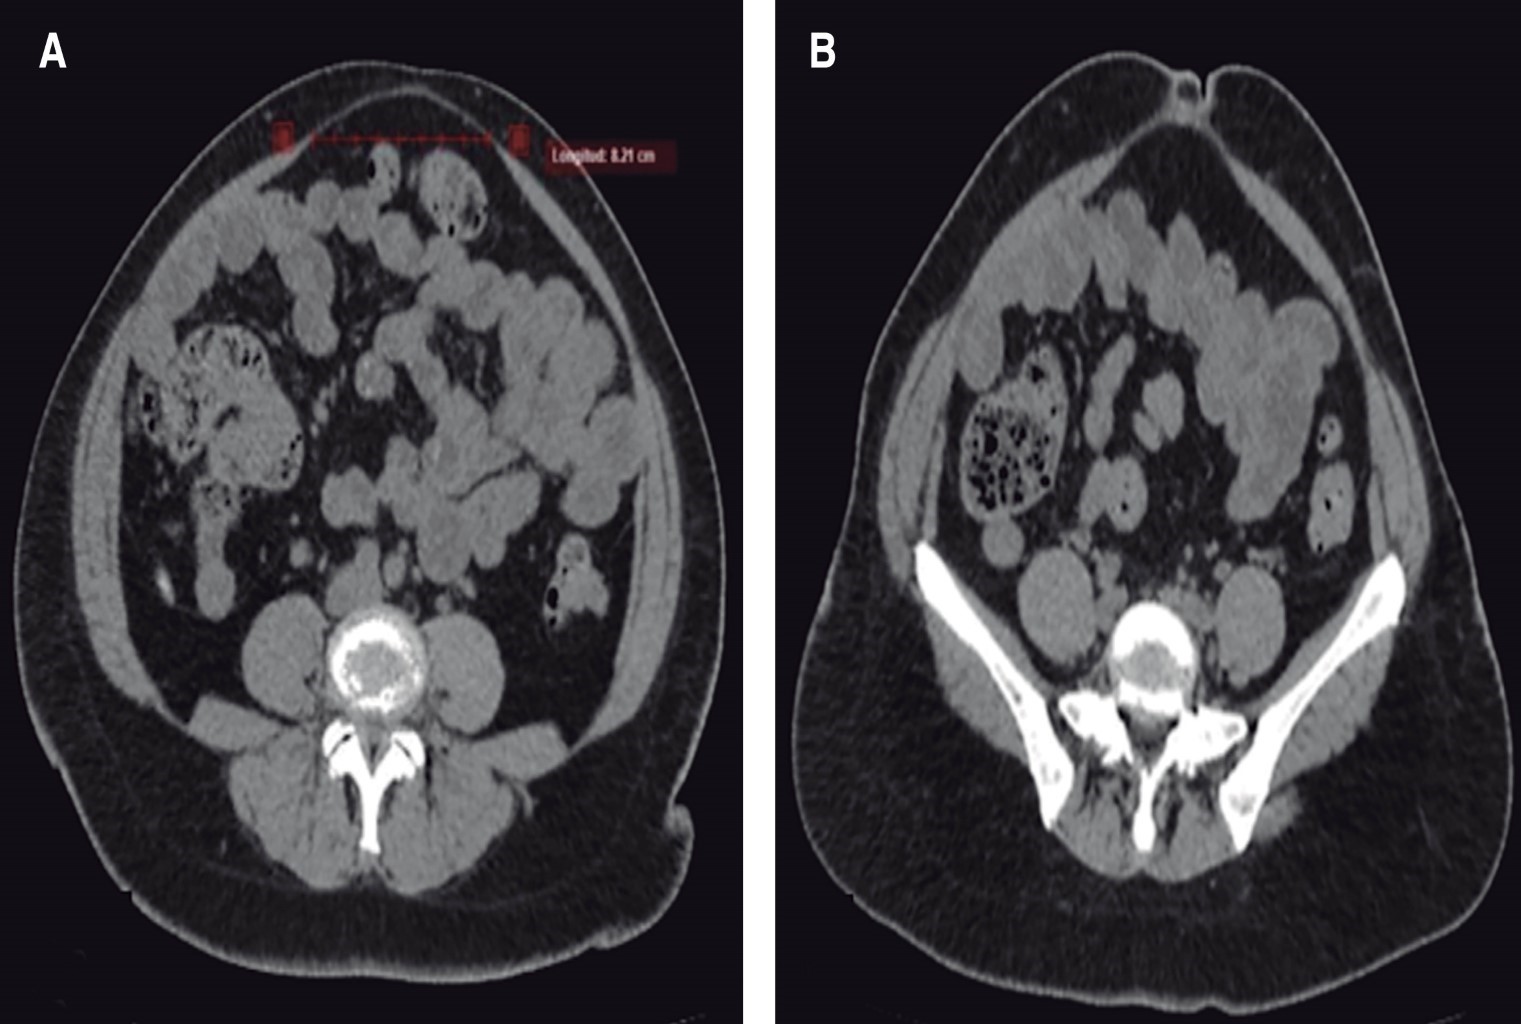

Tras la inspección, se solicita TC de abdomen, la cual se realiza el 03.01.2023, reportando, a nivel supraumbilical, umbilical y justo por debajo de cicatriz umbilical, separación de músculos rectos abdominales de hasta 8.21 cm, fascia abdominal anterior integra, excepto en región umbilical en donde se observa una solución de continuidad de 9.6 mm, con formación de saco herniario de 7.5 × 1.75 mm de contenido epiploico. Se clasifica cómo una diástasis de rectos severa (Figura 2).

Figura 2